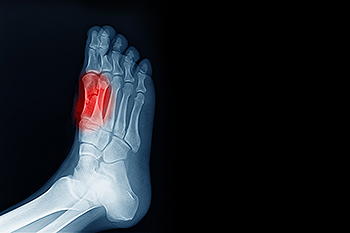

Sesamoiditis Causes and Symptoms

Sesamoiditis is a painful foot condition that affects the sesamoid bones, which are two small bones located beneath the base of the big toe. These bones help absorb pressure and assist with movement during walking and push off. When they become inflamed, pain can develop around the ball of the foot, especially under the base of the big toe. Common symptoms include aching or sharp pain while walking, standing, or bending the toe, along with swelling and tenderness in the area. Sesamoiditis is often caused by repetitive stress, high impact activities, or increased pressure on the forefoot. A podiatrist can diagnose the condition, recommend activity modification, provide protective padding or orthotics, and develop a treatment plan to reduce inflammation. If you have pain under your big toe, it is suggested you schedule a visit with a podiatrist who can accurately diagnose and treat what may be going on.

Sesamoiditis

Sesamoiditis is a condition of the foot that affects the ball of the foot. It is more common in younger people than it is in older people. It can also occur with people who have begun a new exercise program, since their bodies are adjusting to the new physical regimen. Pain may also be caused by the inflammation of tendons surrounding the bones. It is important to seek treatment in its early stages because if you ignore the pain, this condition can lead to more serious problems such as severe irritation and bone fractures.